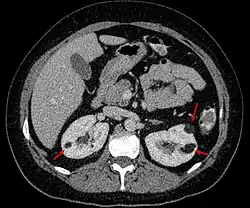

| Angiomyolipoma in both kidneys (arrows) in computer tomography. The tumours are hypodense (dark) due to fat content. | |

Angiomyolipomas are strongly associated with the genetic disease tuberous sclerosis, in which most individuals have several angiomyolipomas affecting both kidneys. They are also commonly found in women with the rare lung disease lymphangioleiomyomatosis. Angiomyolipomas are less commonly found in the liver and rarely in other organs. Whether associated with these diseases or sporadic, angiomyolipomas are caused by mutations in either the TSC1 or TSC2 genes, which govern cell growth and proliferation. They are composed of blood vessels, smooth muscle cells, and fat cells.